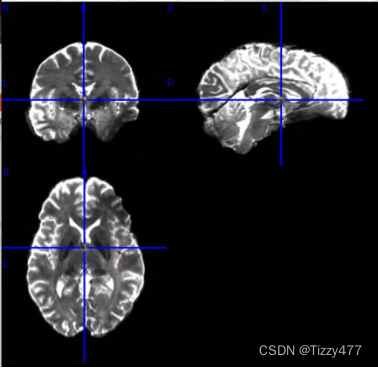

4.创建FA和MD图——使用dtifit函数

dtifit -k $dir_temp/data.nii.gz -o $dir_temp/data -m $dir_temp/nodif_brain_mask.nii.gz -r $dir_temp/bvecs -b $dir_temp/bvals --save_tensor